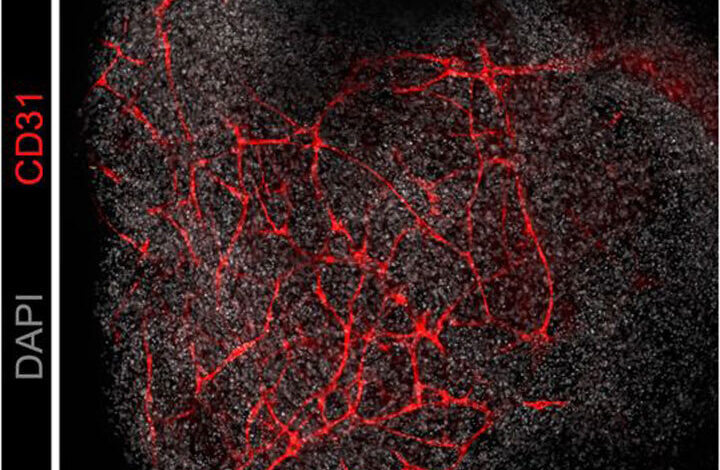

وفي جامعة كاليفورنيا بسان فرانسيسكو، قاموا بزراعة خلايا جذعية بشرية في أطباق بتري لمدة شهرين، مما أدى إلى إنتاج ما يسمى بـ “العضويات القشرية” التي تحاكي القشرة الدماغية النامية. بالتوازي، تم زراعة العضيات من خلايا الأوعية الدموية ووضعها على جانبي العضية القشرية. وبعد بضعة أسابيع، نمت الأوعية بالتساوي في جميع أنحاء الأدمغة المصغرة.

المحاولات السابقة لتوفير الأوعية الدموية للعضويات الدماغية لم تكن قادرة على إعادة إنتاج هذه التفاصيل المهمة، بالإضافة إلى أن شبكة الأوعية الدموية كانت غير متساوية. علاوة على ذلك، في التجربة الجديدة، لا تكون الأوعية الدموية من الناحية الهيكلية فحسب، بل أيضًا من الناحية الجينية أكثر تشابهًا مع تلك الموجودة في الأدمغة النامية الحقيقية، وتشكل حاجزًا دمويًا دماغيًا محسنًا يحمي الدماغ من مسببات الأمراض بينما يسمح للمواد الغذائية والنفايات بالمرور عبرها، كما يشير كيستيماكر.

هكذا نمت شبكة الأوعية الدموية في العضو العضوي بعد 100 يوم من التجربة